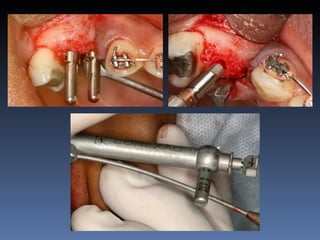

Diagnóstico: Desdentada pré-maxila

Plano de tratamento:        Reabilitação com 2 blocos

“onlay” provenientes de Ilíaco fresco-congelado

(FFB); e posterior reabilitação protética fixa .

Leito nativo atrófico

Preparação e modelação dos blocos

Descorticalização do leito receptor

Fixação dos blocos “ onlay “

Mensuração pós fixação:

Pré - 1,0 mm

Pós – 5,5 mm